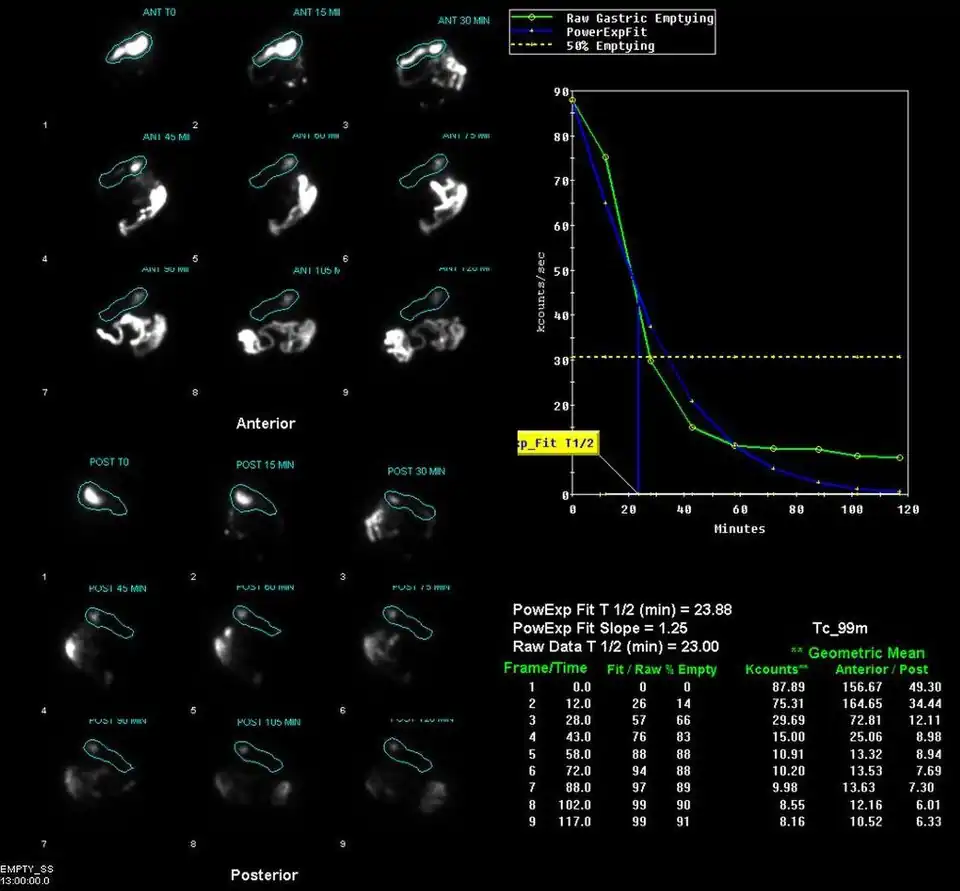

Example gastric emptying images | |

A gastric emptying study is a nuclear medicine study which provides an assessment of the stomach's ability to empty. It may be used if there are complications after gastric surgery, for gastric reflux, or suspected gastroparesis amongst other indications.[1] Scintigraphy that uses gamma cameras to create two-dimensional images is generally regarded as the gold standard for gastric emptying.[2][3]

Having fasted for around four hours before the study, the patient is given a solid or semi-solid meal, such as scrambled eggs on toast or porridge, which has been prepared with a radiopharmaceutical component. Typically technetium-99m sulphur colloid or DTPA is used.[4][1][5] Some studies may also involve a liquid component, which is labelled with indium-111 DTPA.[5] Images are acquired with a gamma camera, initially dynamically and then at intervals for up to 2-3 hours.[1][5][6]

The stomach time-activity curve is produced from geometric mean of anterior and posterior imaging. Half-emptying time, the lag-phase duration for solid studies, and percentage of food left at various time points are calculated.[7]